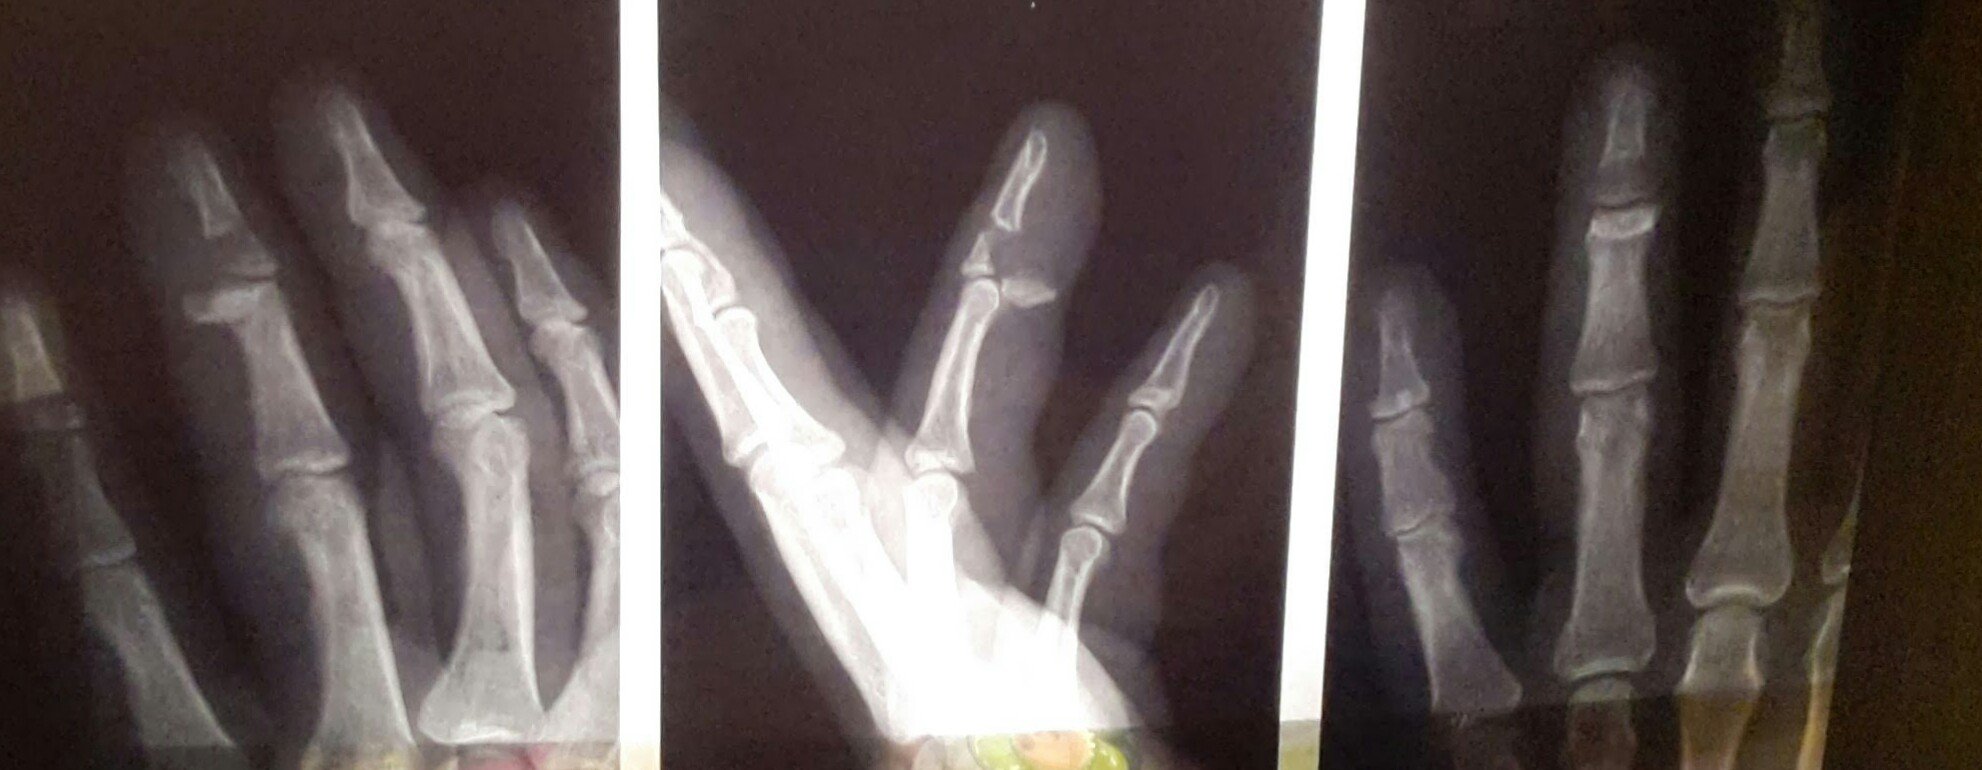

Если в двух словах, то при возвращении с боулинга , в метро, практически на ровном месте, умудрился сломать палец, думал, что ерунда, ан нет, сделал рентген, и ужаснулся, перелом со смещением да ещё по словам хирурга из 4 градской больницы, (куда меня направили из поликлиники) повреждено сухожилие.

• IMG_20131125_213847.jpg

IMG_20131125_213847.jpg

58.3 KB · Просмотры: 333

• IMG_20131125_212214.jpg

IMG_20131125_212214.jpg

174.9 KB · Просмотры: 346